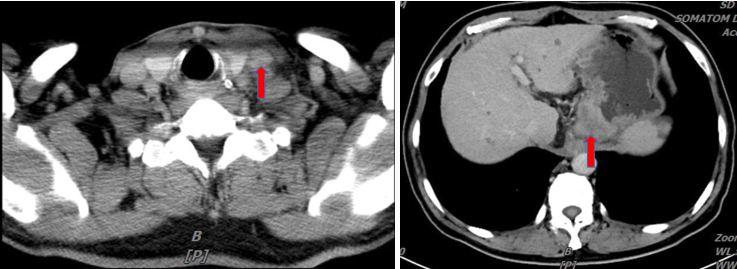

CT:1.贲门癌累及食管下段并腹腔及左锁骨上淋巴结转移;小网膜及肠系膜略增厚,建议观察;2.肝多发结节,建议MR检查以除外转移;3.肝内钙化灶;4.脾大;5.左肾囊肿;6.心腔密度减低,提示贫血;7.右肺下叶结节,转移可能,建议观察;双肺少许炎症及纤维灶;8.前列腺钙化灶;9.副鼻窦炎。

临床诊断:1.食管胃结合部癌(腺癌,Her-2阴性,pMMR,cT3N1M1,Ⅳ期) ;2.左锁骨上淋巴结、腹腔淋巴结转移;3.贫血;4.乙型病毒性肝炎。

患者于2022-01-07至2022-5-17行FOLFOX方案(奥沙利铂+5-FU+亚叶酸钙)+纳武利尤单抗7周期,在第5周期后复查CT(2022-04-06 )提示贲门癌累及食管下段,较前(2022-02-24)略饱满,盆腔积液较前增多。考虑疗效欠佳,于2022-4-19至2022-5-25联合放射治疗(贲门、患侧胃、及胃周淋巴引流区IMRT,DT 200cGy/次×28)。